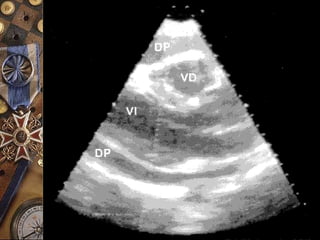

ECOCARDIOGRAFÍA  Es unexcelente método para el diagnóstico  Confirma la presencia de derrame pericárdico y brinda datos sugestivos de taponamiento cardiaco  La ausencia de pruebas ecocardiográficas de derrame pericárdico excluye virtualmente el dx de taponamiento

TAPONAMIENTO CARDÍACO  Enausencia de derrame imposible  Bamboleo cardíaco  Colapso de VD ( Especificidad = 100%)  Colapso de AD ( Sensibilidad = 100%) ECOCARDIOGRAMAECOCARDIOGRAMA